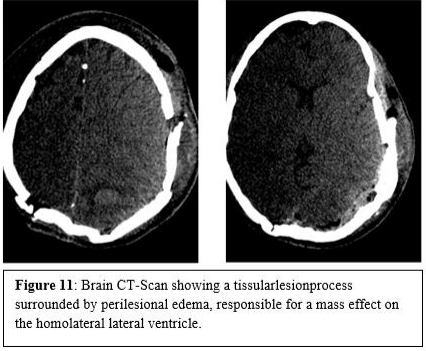

The patient was subsequently referred to the hematology department for possible management. Clinically, the patient was conscious, the neurological examination showed a right hemiparesis and limited oculomotricity of the left eye. Meningitis occurred in the postoperative period. The CSF analysis showed hypoglycorrhachia at 0.44 g/l and hyperproteinorrachia at 0.55g/l with isolation of staphylococcus homanis sensitive to ciprofloxacin and vancomycin. An extension work-up with cervico-thoraco-abdomino-pelvic CT and osteomedullary biopsy was negative. The patient had undergone a postoperative CT-scan which revealed a persistent extra-axial tissular lesion process measuring 38x32x28mm, spontaneously hyperdense, in the left occipital region, surrounded by perilesional edema, responsible for a mass effect on the homolateral lateral ventricle associated with significant infiltration of the soft tissues of the scalp Figure11.